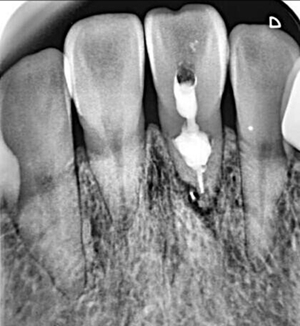

牙內(nèi)吸收通常無明顯癥狀。根據(jù)吸收的類型和原因,主要分為炎癥性吸收和替代性吸收。其中,炎癥性吸收可能繼發(fā)于前期牙本質(zhì)的細(xì)菌感染和創(chuàng)傷,牙本質(zhì)吸收過程的進(jìn)展不伴有吸收區(qū)鄰近部位硬組織的沉積,吸收部位可見大量肉芽組織,典型的影像學(xué)表現(xiàn)為,以根管為中心的橢圓形透光區(qū)。替代性吸收,導(dǎo)致根管內(nèi)牙本質(zhì)缺損的同時,在缺損區(qū)某些部位還伴有骨樣組織的沉積,造成牙髓腔不規(guī)則的擴(kuò)大和根管連續(xù)性的破壞。根據(jù)牙內(nèi)吸收發(fā)生部位和嚴(yán)重程度的不同,又可呈現(xiàn)不同的征象。若吸收部位發(fā)展至牙冠,可以觀察到牙冠上出現(xiàn)粉紅色的點,這是吸收細(xì)胞鄰近的結(jié)締組織高度血管化的結(jié)果。當(dāng)吸收部位位于根方,則可使得根管原有的形態(tài)缺失,X線片可見根管局部氣球樣的膨大,通常邊界清晰。若牙髓還有部分的活力,則患牙可能有慢性牙髓炎的表現(xiàn);若牙髓完全壞死,則可能發(fā)展成根尖周炎,而出現(xiàn)相應(yīng)的癥狀。竇道的出現(xiàn)往往是己發(fā)生慢性根尖膿腫或根管側(cè)穿的表現(xiàn)。由于患牙冠方的牙髓通常己經(jīng)壞死或被去除,因此敏感性測試常為陰性。

牙內(nèi)吸收一旦確診,則需要對患牙的預(yù)后做出判斷。對于有保留價值的患牙,應(yīng)該及時行根管治療。對于未發(fā)生根管側(cè)穿者,應(yīng)完全去除根管內(nèi)吸收組織,以防止其牙體硬組織的進(jìn)一步破壞。牙內(nèi)吸收所導(dǎo)致的病損的特點,給根管治療帶來了難度。行根管預(yù)備時,應(yīng)盡量保守,以最大程度的保留牙體組織,以免對本就薄弱的根管壁造成進(jìn)一步的損害。對于有活動性吸收的患牙,在治療過程中,炎癥牙髓和肉芽組織可能出現(xiàn)大量的滲血從而影響操作視野。同時,機械預(yù)備的方法往往不能完全達(dá)到吸收所造成的缺損部位。因此,根管預(yù)備時次氯酸鈉和超聲設(shè)備的作用就顯得尤為重要。次氯酸鈉可以溶解壞死的牙髓組織。超聲的震蕩可以使次氯酸鈉沖洗液活化,并充分滲透到根管系統(tǒng)的每個角落,以減少根管內(nèi)細(xì)菌的數(shù)量。然而,即使使用了超聲設(shè)備,往往根管內(nèi)局部還是會有細(xì)菌的殘留因此,根管內(nèi)封藥應(yīng)該具有良好的抗菌作用,以提高器械所不能到達(dá)部位的消毒。氫氧化鈣糊劑對根管內(nèi)多種細(xì)菌有殺傷作用,并可滲入牙本質(zhì)小管發(fā)揮殺菌作用,效果明顯。此外有研究證實,氫氧化鈣與次氯酸鈉有協(xié)同作用,可減少根管內(nèi)有機碎屑的殘留囚。對于根管的充填,應(yīng)選擇具有良好流動性的充填材料,來封閉吸收所造成的缺損。其中,熱塑性牙膠充填技術(shù)最為常用。

在一些病例中,牙內(nèi)吸收己經(jīng)發(fā)展至牙根外表面,使得根管與牙周相連通,并可能出現(xiàn)鄰近牙周組織的病變。這就需要在根管治療的同時行穿孔的修補。礦物三氧化物凝聚體(mineral trioxide aggregate,MTA)具有良好的生物相容性和誘導(dǎo)成骨性,對根尖周組織的刺激小,并且和其他材料相比,其封閉性也更好,故常用來做穿孔的修補。當(dāng)牙內(nèi)吸收的缺損不可修復(fù)時,則只有選擇拔除。